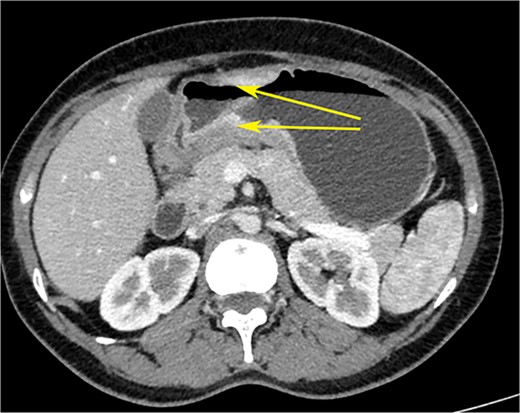

CT scan of the abdomen showing gastric wall thickening at the level of the pyloric antrum (yellow arrows).